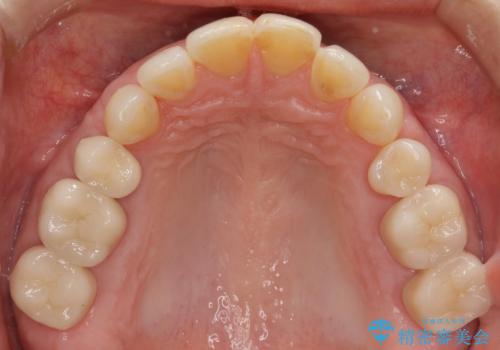

口の中の金属を外したい セラミッククラウンによる治療

銀歯・虫歯を丁寧に除去したのち精密なセラミック治療を行うことで長期的な予後を目指します。

- 57万円(仮歯・ファイバーコア・ジルコニアクラウン×5)費用は治療当時の料金となります

銀歯をを外すだけでなく、セラミックを適合よく精密に製作することで長期的な予後を見込むことが可能になります。